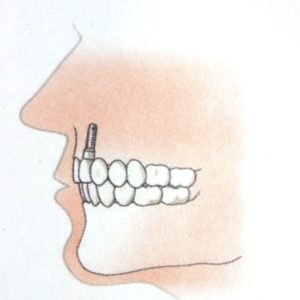

- Bij het ontbreken van één tand of kies, wordt een implantaat ter plaatse van het ontbrekende gebitselement in de kaak geplaatst en wordt daarop een kroon van keramiek of een combinatie van keramiek met metaal vastgezet..